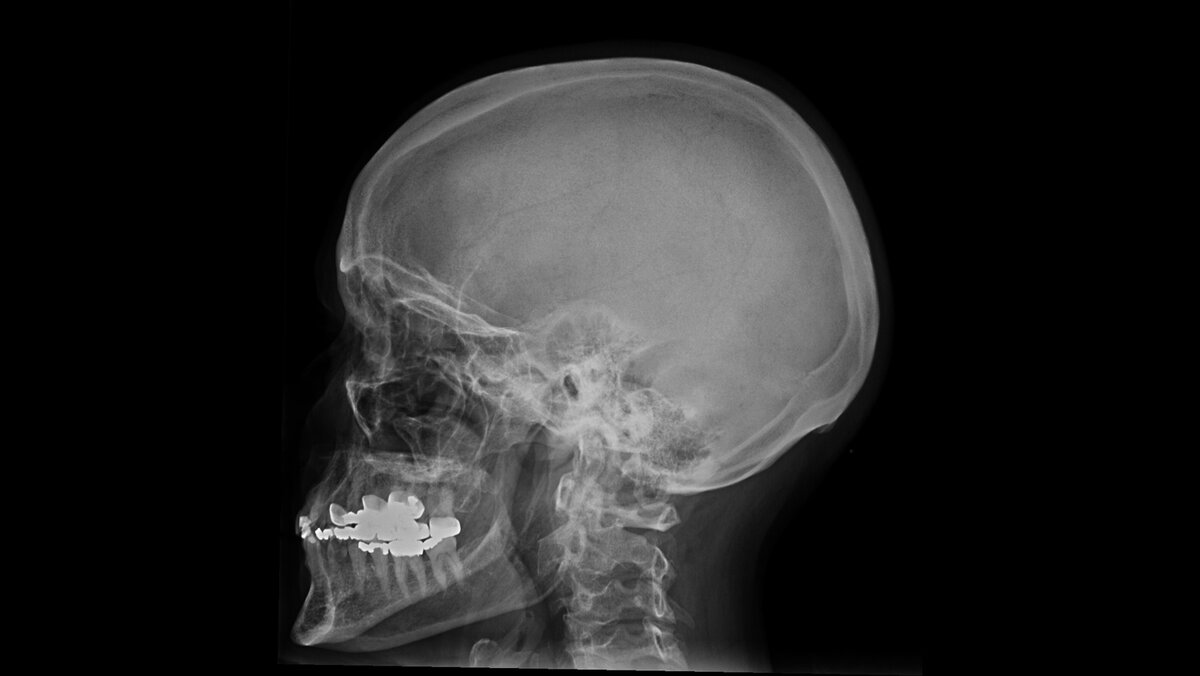

• рентгенография черепа – в основном выполняется для получения первичных представлений о природе обнаруженной очаговой неврологической симптоматики, так как она может быть обусловлена не только опухолью, но и травмами, кровоизлияниями в мозг, пороками развития и т.д. В ряде случаев на рентгенограмме можно увидеть опухолевую деструкцию костей или отложения кальция в ткани опухоли;